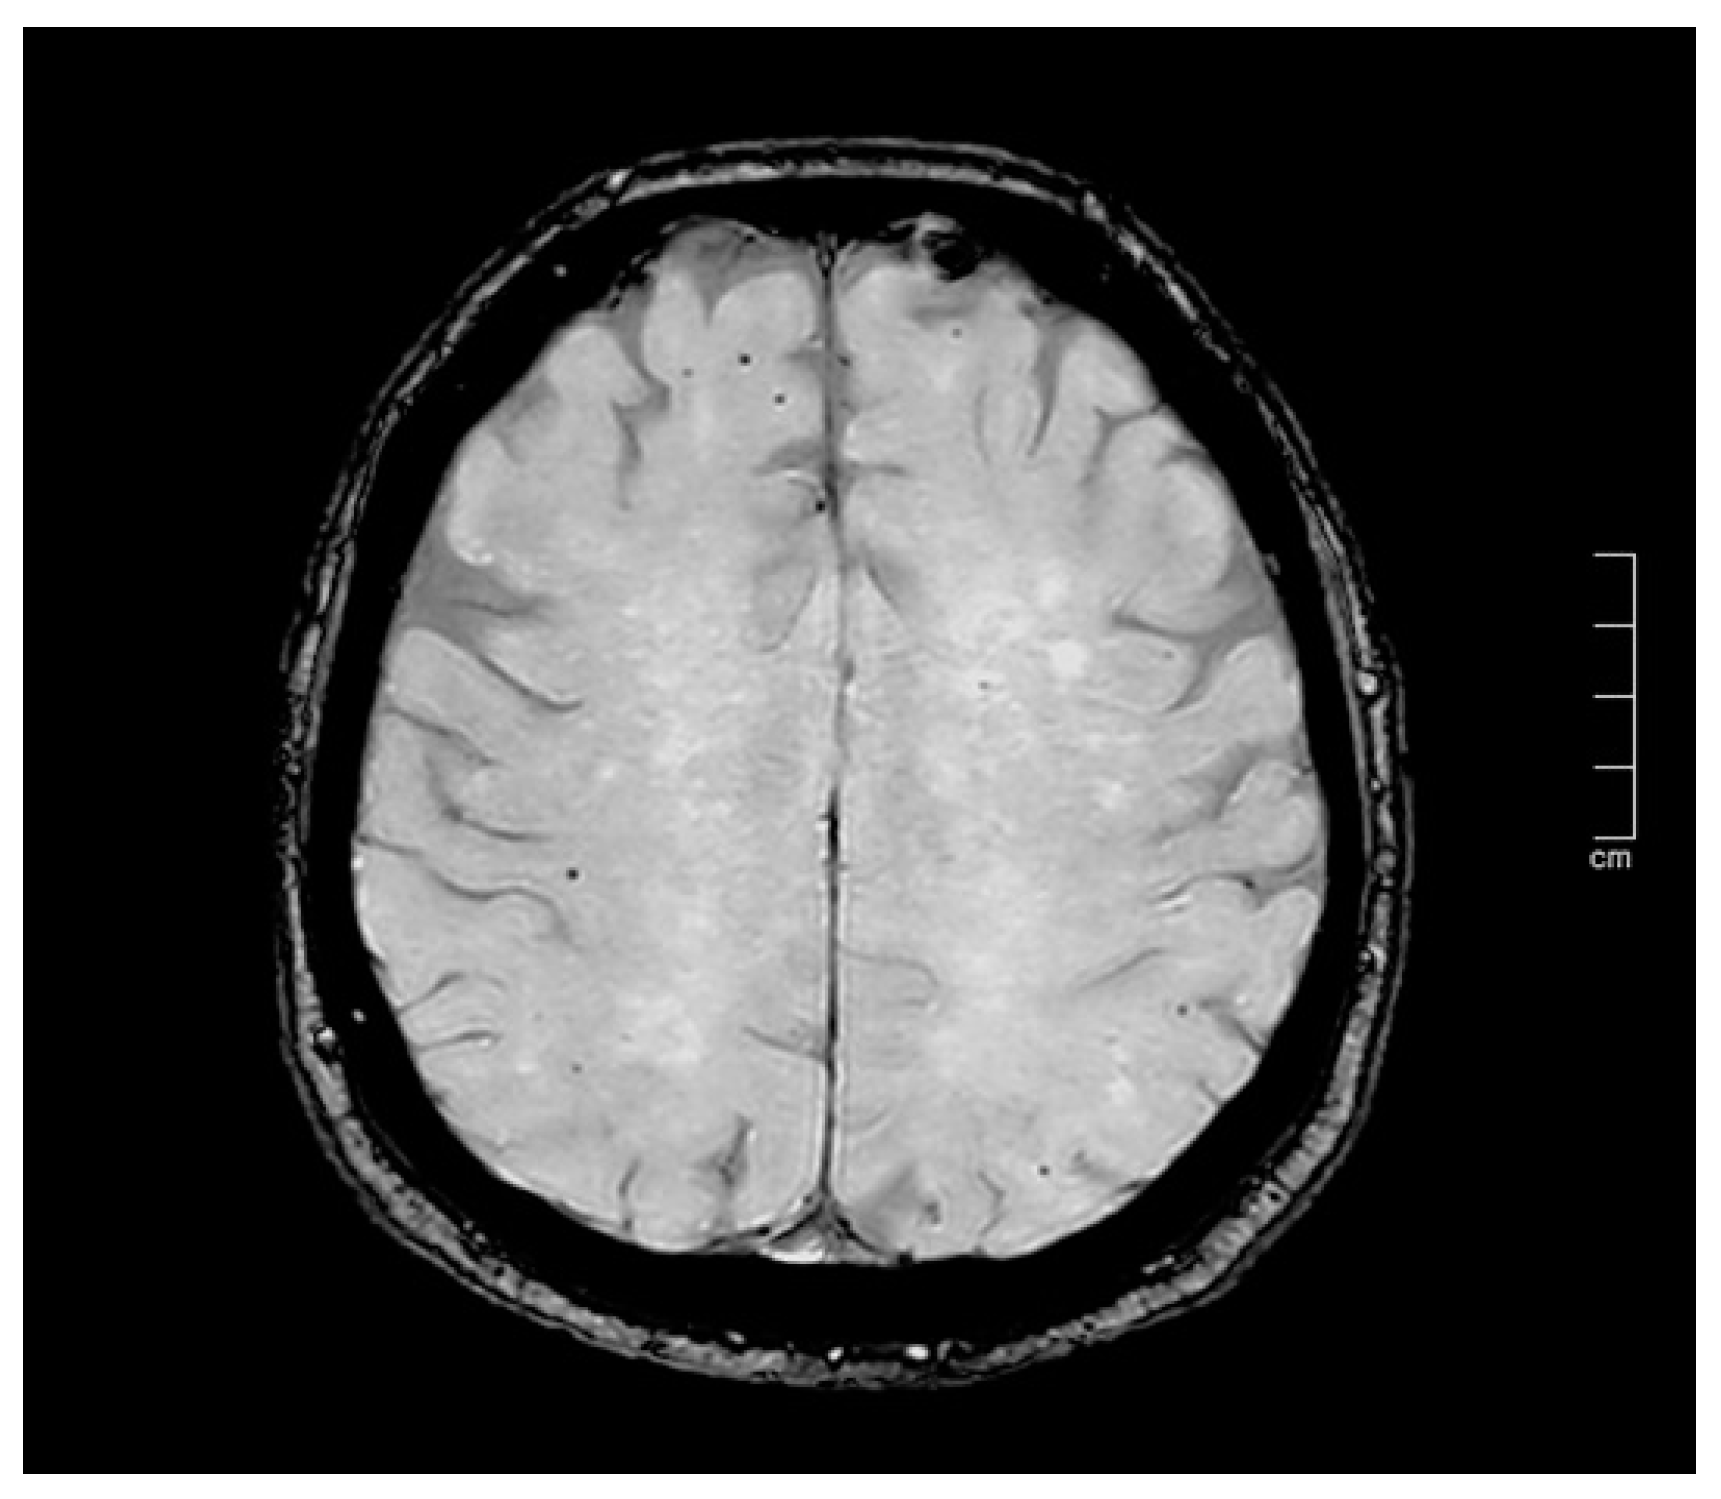

4.2. The Accuracy of MR Imaging—A SWI Technical Note

| Neuroimaging technique for CMBs | Imaging sensitivity is crucial: SWI is more sensitive than T2*-weighted gradient echo for CMB detection. |